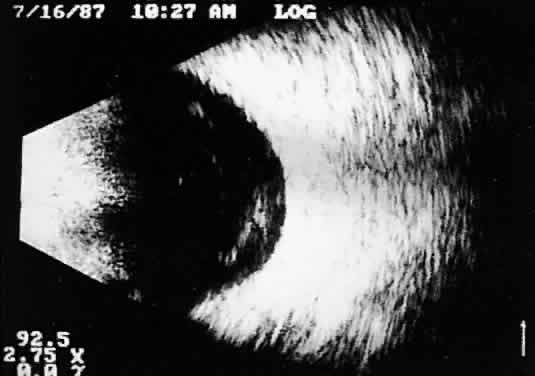

is an important measurement for initial and follow-up examination.10 TUMORS A-scan tumor characterization is often extremely helpful to the clinician. A thorough understanding of ophthalmic pathology is critical to interpretation and often predictive of typical A-scan tumor patterns. Choroidal malignant melanoma, perhaps the most widely studied intraocular mass lesion, has the most reproducible and reliable A-scan pattern. Usually, the initial echo seen in A-scan is a high-amplitude spike secondary to the strong vitreoretinal surface echo overlying the tumor mass. Once the examining sonic beam has passed into the tumor tissue, a rapidly declining amplitude cadence is noted, a consequence of increasing ultrasonic tissue homogeneity. Clinical knowledge of the typical microscopic tumor pattern of tightly packed, homogeneous small cells makes anticipation of relatively low reflectivity possible (Fig. 10). This same low-amplitude reflectivity in B-scan imaging produces a picture that makes the melanoma mass appear hollow. Often, tumor-infiltrated choroid also appears dark (Fig. 11). This change in the normally highly reflective choroidal tissue is widely but inaccurately called choroidal excavation. The terms “hollowing” and “choroidal excavation” are misleading because these tumors are not hollow and the choroid is not excavated. Nevertheless, these terms have been used so frequently in past literature that any change in vocabulary is unlikely.